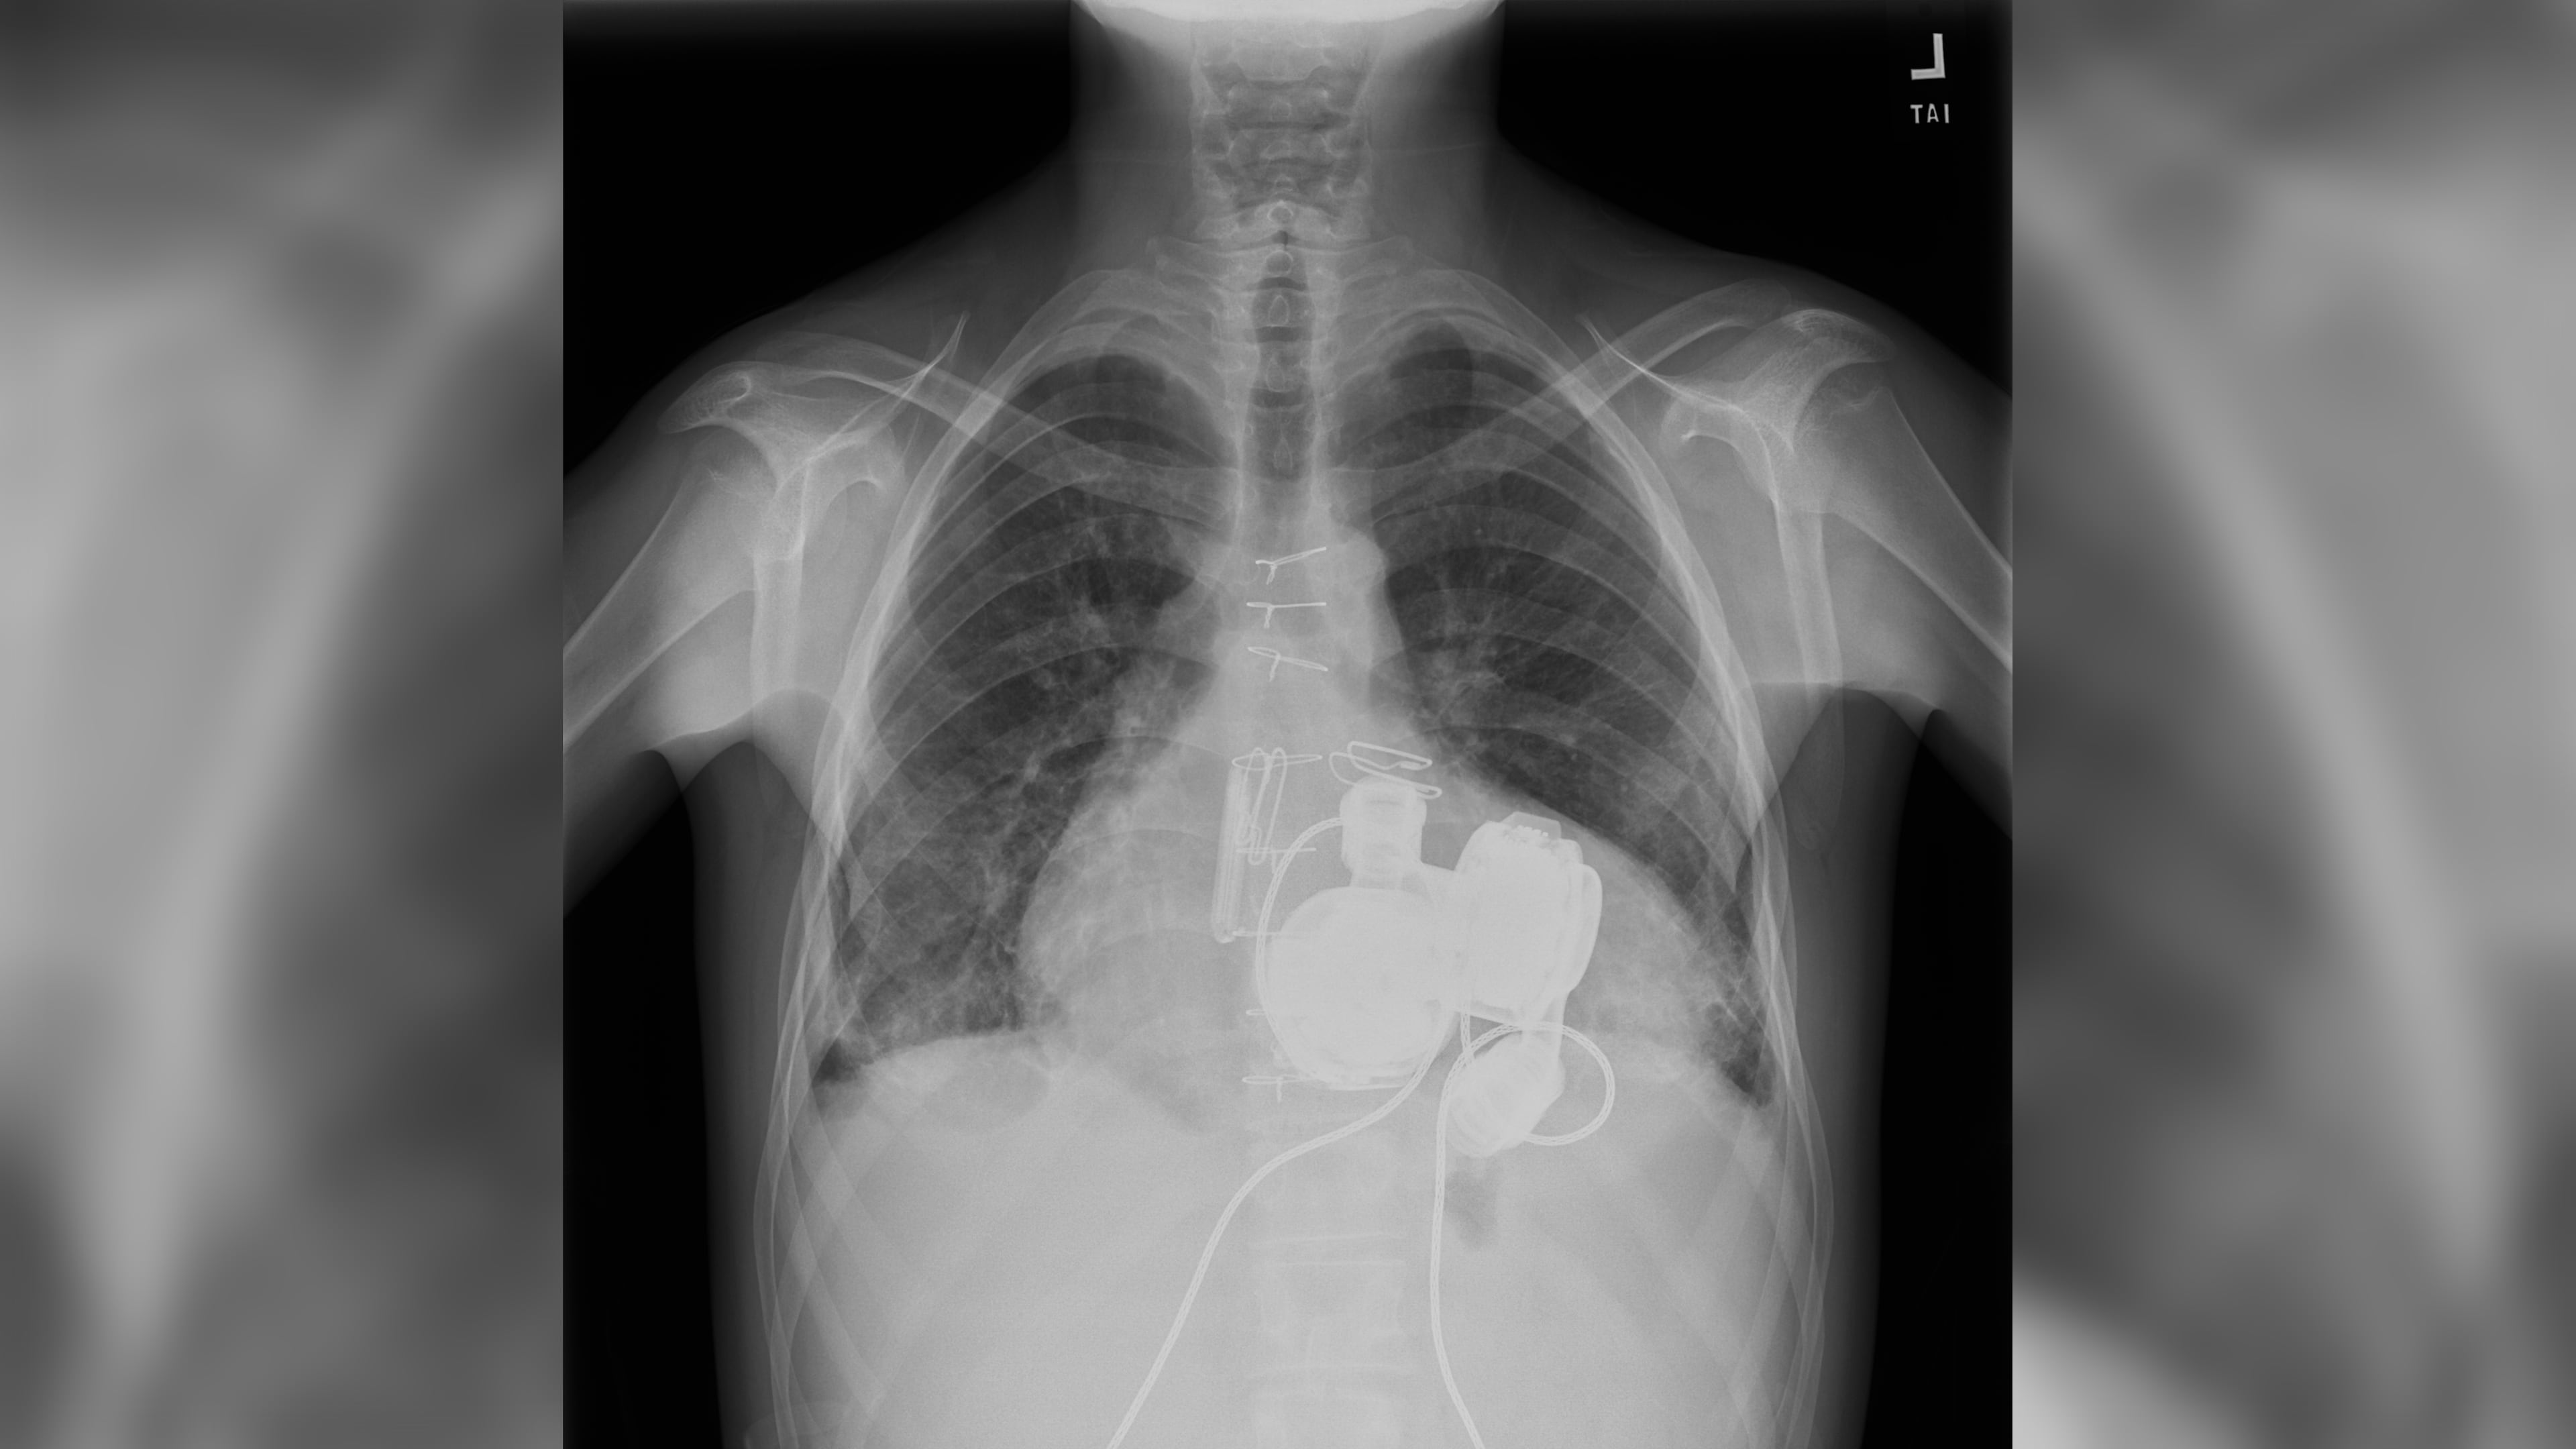

To address this need, Daneshmand designed a procedure called “HeartMate 6,” which combines two HeartMate 3 pumps, mechanically circulatory support devices made by Abbott Health, to support both sides of the heart simultaneously.

This summer, soon after Miles graduated from high school, Daneshmand implanted the two HeartMate 3 devices to support both the left and right sides of his heart. Instead of a temporary procedure that leaves the heart structures intact, Daneshmand’s total artificial heart procedure removes some of the ventricle before inserting the ventricular assist device.

He believes the artificial heart configuration works better than the temporary procedure because there’s a reduced chance of failure from stagnating blood causing a clot, which is common if the right ventricle isn’t removed.